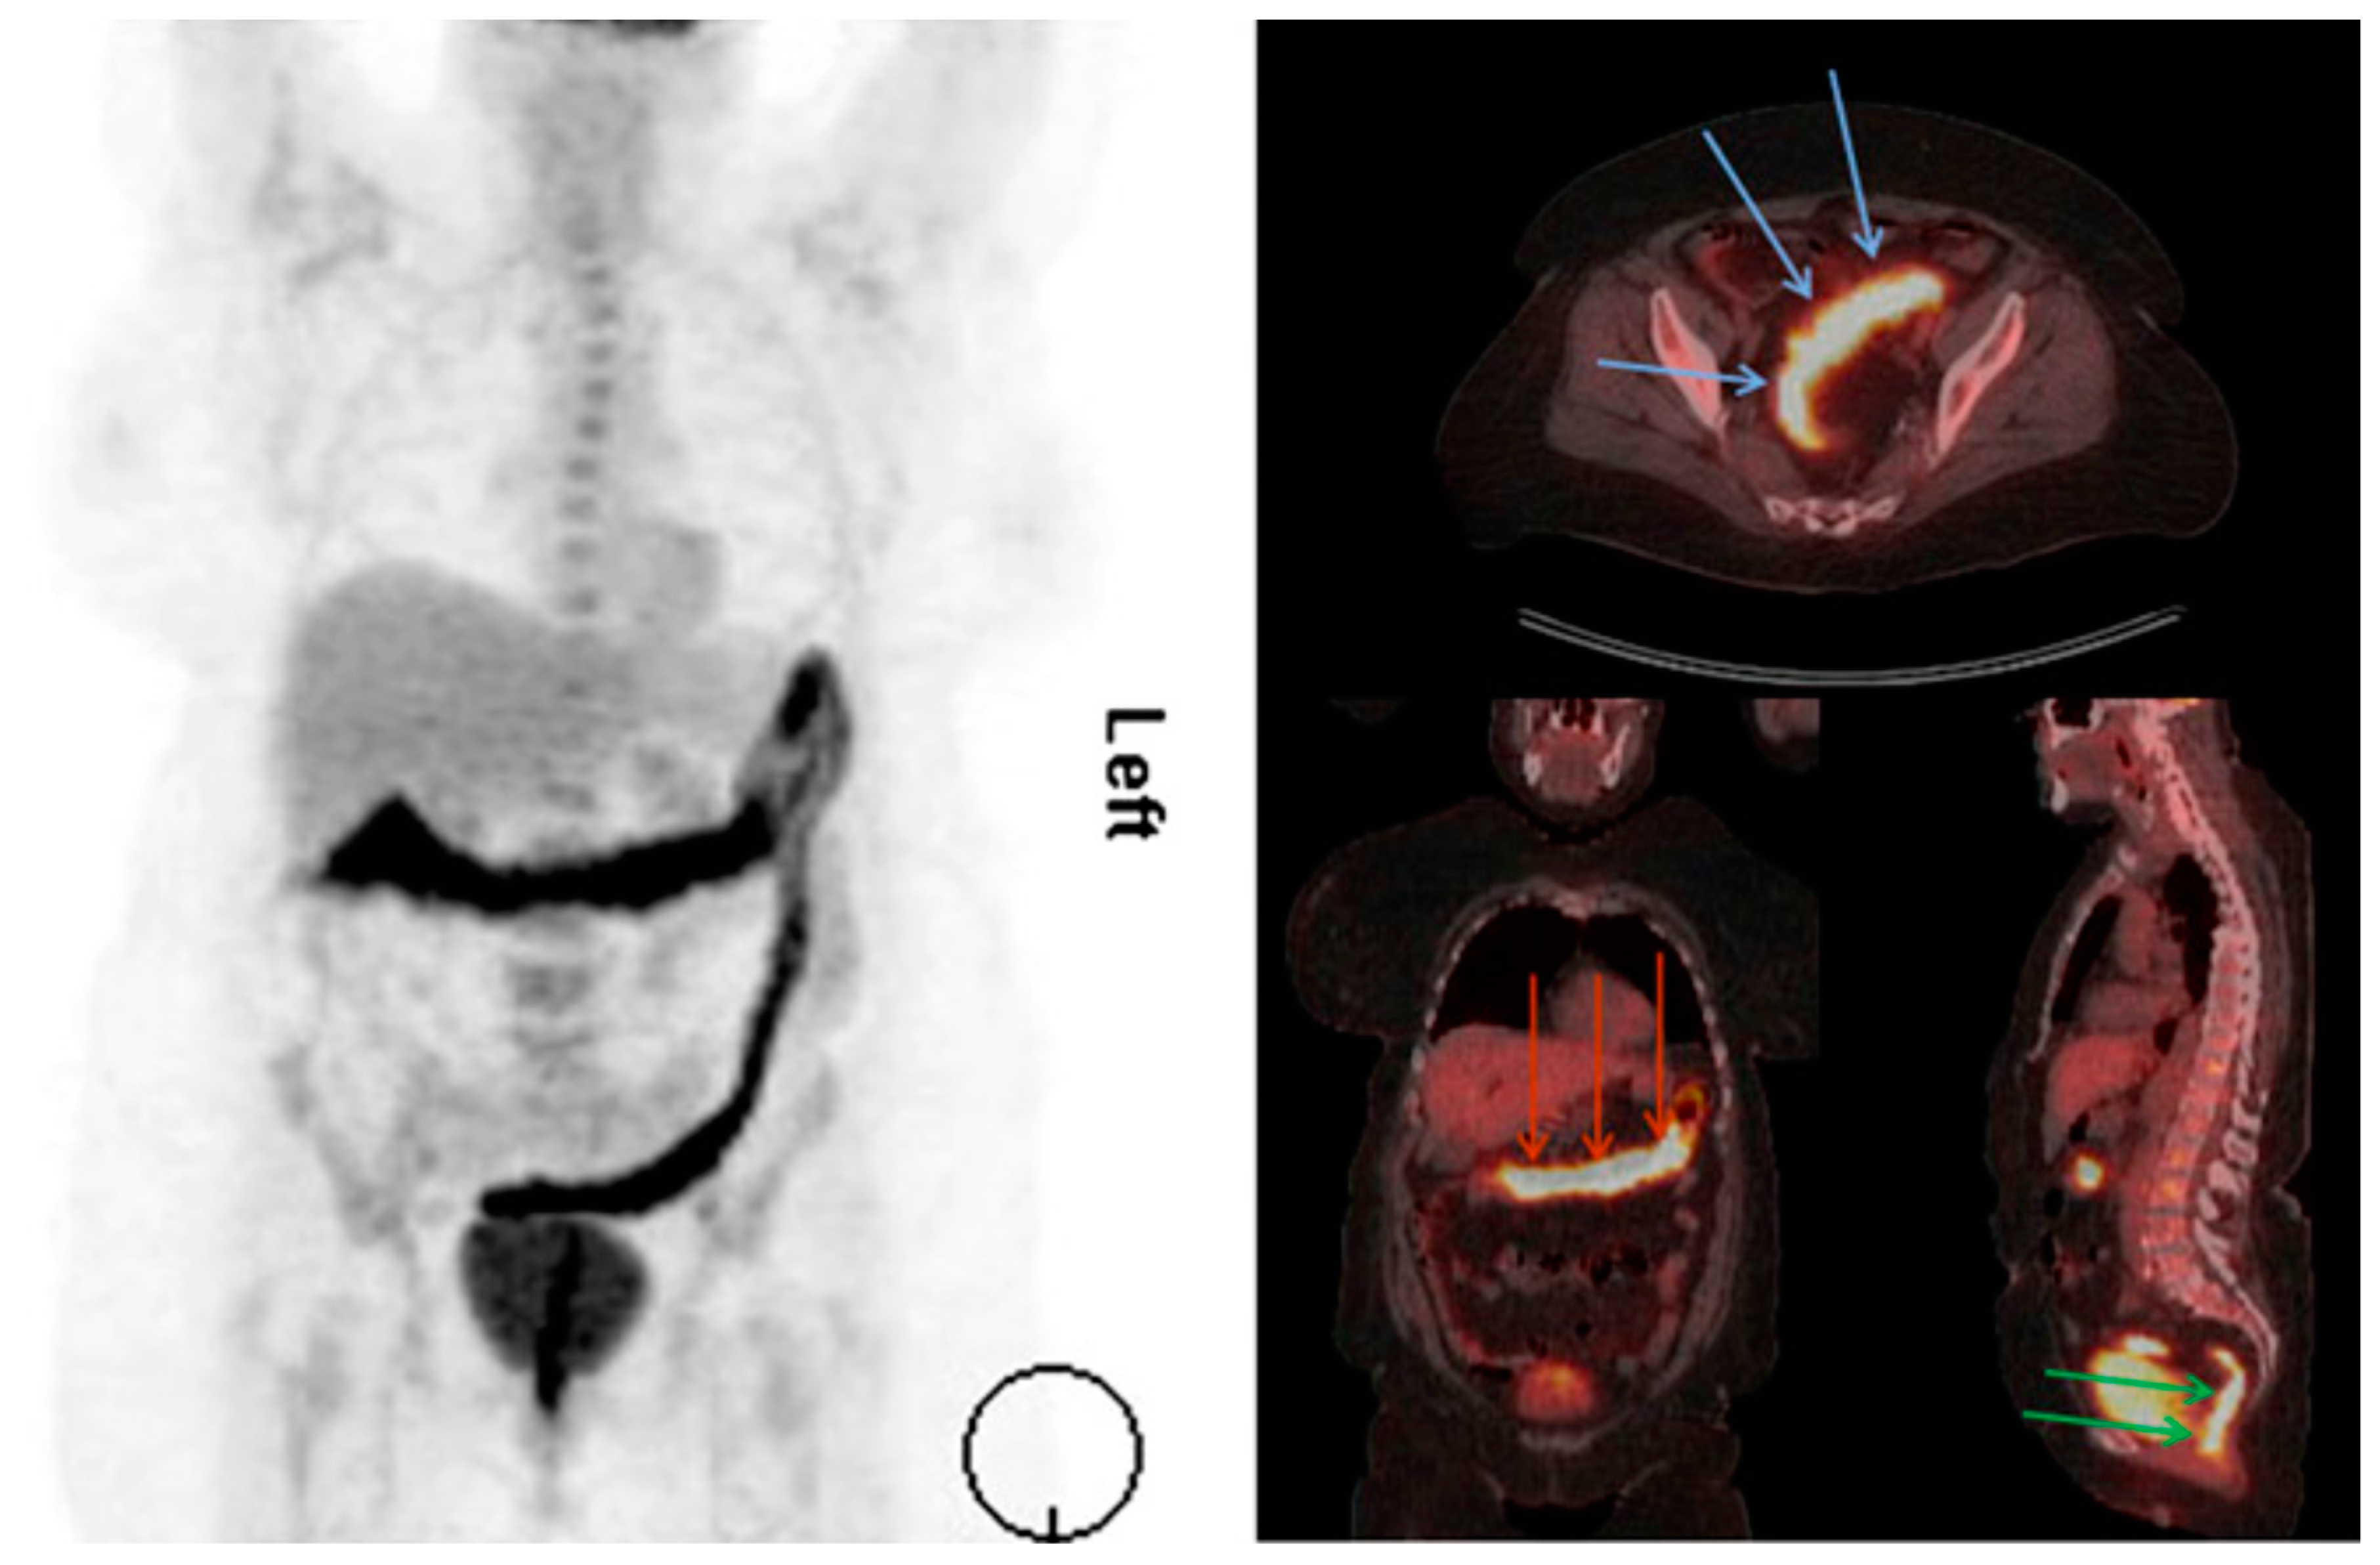

3.2.4. Positron Emission Tomography

3.2.5. Immuno-PET